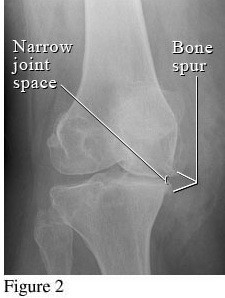

Hình ảnh so sánh giữa khớp bình thường và khớp bị thoái hóa khớp gối

Để phân biệt các giai đoạn của bệnh thoái hóa khớp gối, cần dựa vào phim X- quang theo tiêu chuẩn chẩn đoán thoái hoá khớp của Kellgren và Lawrence như sau:

3. Giai đoạn 3: Thoái hóa khớp gối độ 3

Hình ảnh của khớp gối trên phim X-quang: Khe khớp hẹp rõ, nhiều gai xương kích thước vừa, đặc xương dưới sụn, đầu xương có thể bị biến dạng.

Thoái hóa khớp gối tiến triển đến giai đoạn 3 thì bệnh nhân sẽ càng cảm nhận rõ những cơn đau tại khớp gối. Các lớp sụn khớp bao bọc các đầu xương bị bào mòn nhiều và khoảng không gian giữa các đầu xương bị thu hẹp thấy rõ. Khả năng đi bộ của người bệnh giảm, đi, đứng, ngồi xổm, lên xuống cầu thang cũng thấy đau. Tình trạng cứng khớp vào buổi sáng cũng xảy ra thường xuyên hơn kèm theo các đợt viêm khớp gối (sưng, đau, tràn dịch) hoặc có biểu hiện vẹo khớp gối.